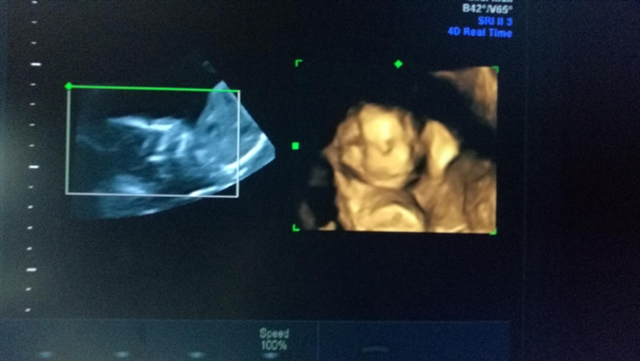

孕29周+5天

孕27周+1天